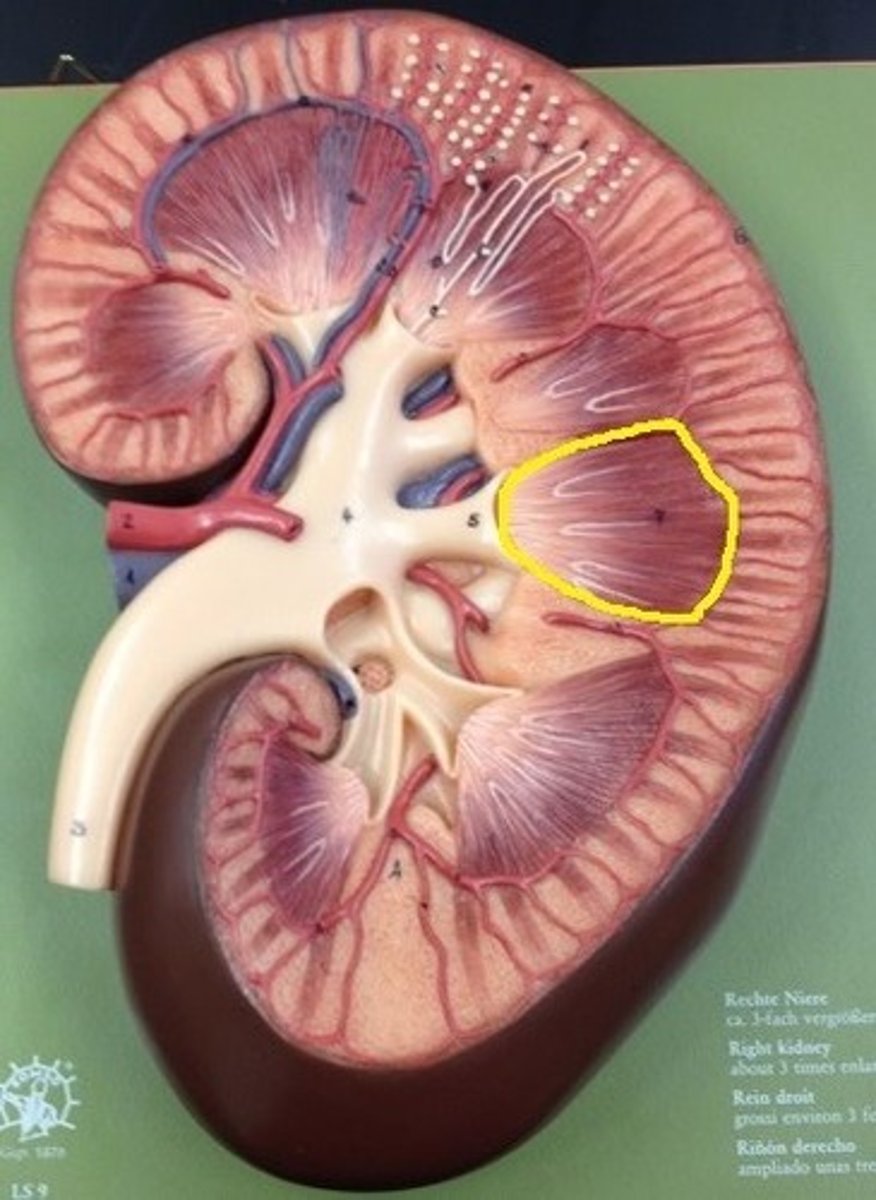

renal medulla

inner region of the kidney

renal pyramids

striated triangular-shaped areas of tissue in the medulla of the kidney

medullary area of the renal pyramids where collecting ducts empty urine into the minor calyces